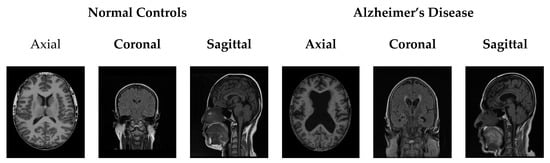

Initially, images for both NC and AD patients were obtained from Chettinad Hospital. Based on the doctor’s contribution, this study took into account around 200 images from real-time public databases. AD is a neurological/neuropathological illness that affects brain structures and produces a variety of cognitive impairments, including increased confusion, loss of knowledge, impairment in memory skills, and difficulties comprehending and performing activities. As a result, there is a need to focus on the brain’s interior areas, such as the ventricle, CC, GM, HC, and WM, when analyzing AD. The suggested system considers all three slices (axial, coronal, and sagittal) of the encephalon/brain to segment all of the above-mentioned areas. Figure 2 shows the raw pictures of all three slices of NC and AD images. Because of anatomical differences, the encephalon’s inner tissues are very small and difficult to distinguish. Because the interior parts of the brain have undefined borders and have relatively low contrast, they must be preprocessed.

Figure 2.

Input images of NC and AD with different slices.